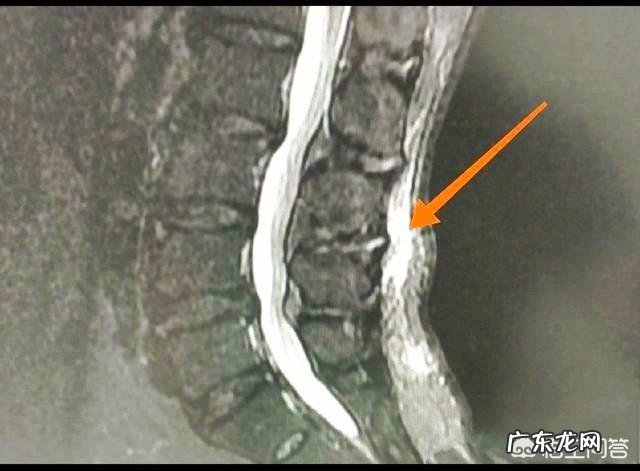

现在腰骶疼痛的疼痛经常的发生,据了解,至少有一半以上的人有过或者正在经受腰痛,站立时间久了会腰痛,扭伤了会腰痛,腰间盘突出了也会腰痛,各种各样的原因都引起腰部疼痛,下图就是一位腰痛的患者,磁共振检查发现是背部浅筋膜炎:

1、腰肌劳损:腰肌劳损是比较常见的腰痛的原因,分为急性和慢性,急性腰肌劳损多是在搬重物时突然间发生,腰痛不能扭转 。慢性劳损病程较长,跟平时的工作运动习惯等有很大的关系 。一般腰肌劳损的x线检查没有异常,或者仅见骨质增生,需要磁共振检查可以发现肌肉水肿,肌腱附着点损伤,或浅筋膜炎等等 。